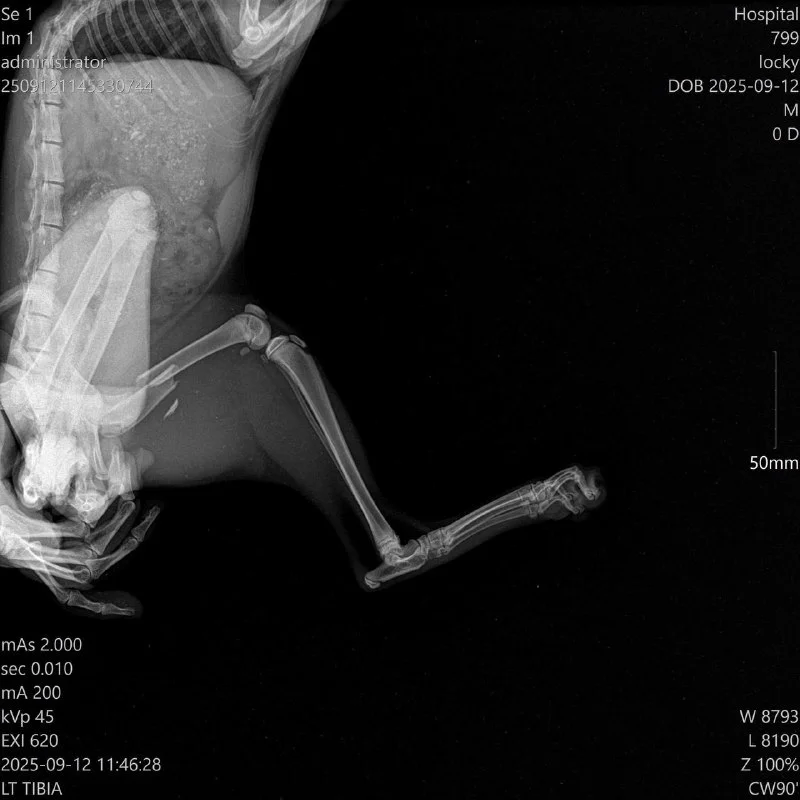

Неделю назад в пятницу 12/09 мне написала Биляна - с просьбой помочь отвезти рыжего кота со сломанной лапой в клинику.

Отнесли к Мариносу. По рентгену видно, что перелом сложный, но доктор сработал профессионально и оперативно (не зря говорят, что в плане хирургии у Мариноса - золотые руки!) и теперь у котика титановая пластина в лапке, благодаря которой сращивается кость 💙 🐾

Котик молодой, ему нет и года - но реабилитация такого сложного перелома - это 4-6 недель, в которых надо ограничить движение.